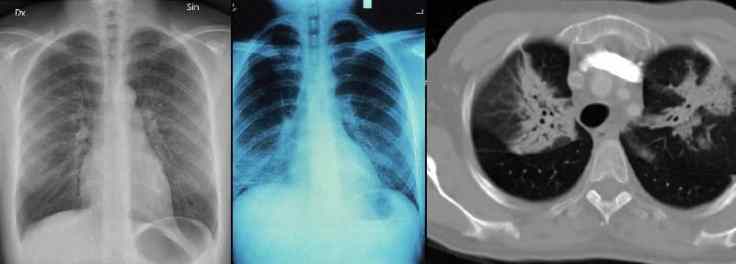

X-rays and C.T scans are amazing pieces of technology. One that I get the impression to many people have an ill informed fear of. I don’t say unfounded, because yeah, to much radiation can be dangerous.

But, I think people’s fear of having “to many” x-rays and C.T scans, exaggerates the danger beyond what it actually is. If you have lung issues… (In my purely personal, un-medically educated opinion.) the diagnostic benefits of X-rays far outweighs the potential risks involved.